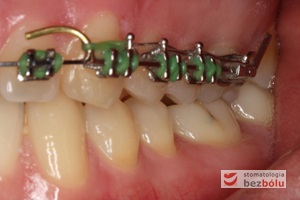

Młody 28-letni, pogodny, stale uśmiechnięty pacjent zgłosił się celem korekcji wad zębowych ograniczających pełną ekspresję uśmiechu. Głównym problemem był dodatkowy siekacz boczny (dwójka) po stronie prawej w łuku górnym. Dodatkowy ząb spowodował stłoczenia pozostałych zębów w łuku górnym oraz przesunięcie linii pośrodkowej. Obliczenia dostępnego miejsca dla siekacza bocznego wpłynęły na wybór zęba przeznaczonego do ekstrakcji. Usunięto dwójkę ustawioną dowargowo, zaś jej „siostrę bliźniaczkę” skierowaną w stronę podniebienia wprowadzono do łuku zębowego w drodze leczenia ortodontycznego. Problemem było szczelne zamknięcie szpary poekstrakcyjnej z powodu nadmiaru miejsca w kości. Wyrównano linię pośrodkową. Leczenie przeprowadzono jednym łukiem ortodontycznym górnym, dolny łuk zębowy nie wymagał założenia aparatu. Po zdjęciu zamków korekcję detali przeprowadzono z użyciem pozycjonera wykonanego w technice termoformingu. Stabilizację efektów leczenia zapewnił stały retainer klejony do powierzchni podniebiennych siekaczy górnych.